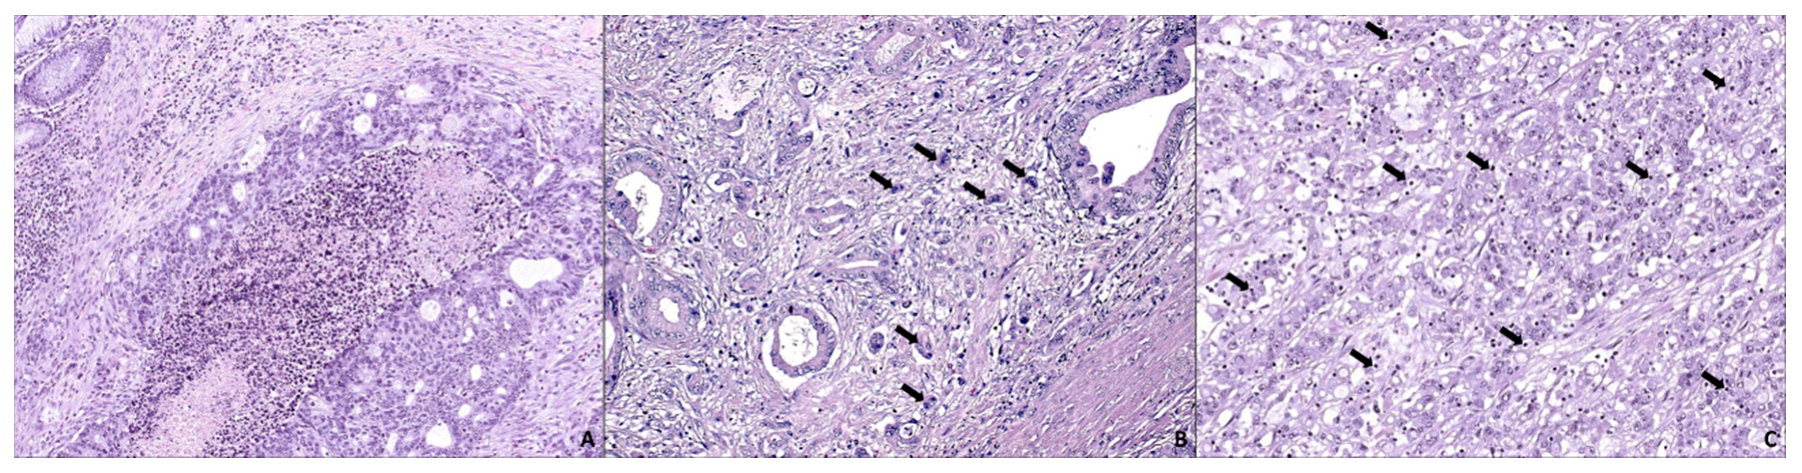

4. SAC Displays an Active Invasive Front